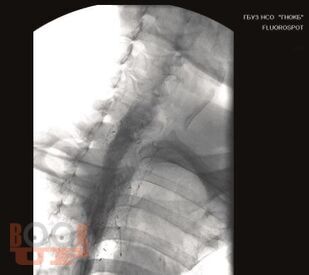

Эндоскопическая диагностика заболеваний верхних отделов желудочно-кишечного тракта у детей

В пособии отражены современные представления о вопросах диагностической и оперативной эндоскопии верхних отделов желудочно-кишечного тракта. Изложены виды эндоскопических исследований и вмешательств, эндоскопическая семиотика заболеваний пищевода, желудка, двенадцатиперстной кишки, особенности «эндоскопической нормы» органов желудочно-кишечного тракта.